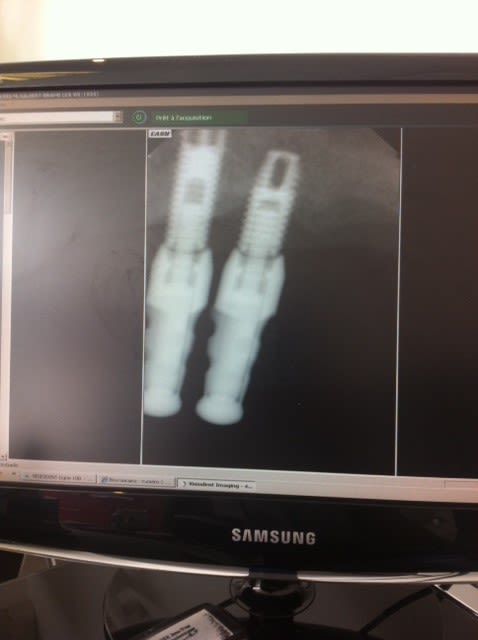

bonjour j ai recupéré un cas j ai posé deux implants 27,28et je doit me servir de ces deux la pour faire un bridge24,28

Problème: le patient m'a dit que c'était du branemark j ai commandé les pièces adéquates avec un conseiller nobel .

Patatras les pilers flottent j ai contacté un responsable NOBEL qui m a dit que c'était pas du Branemark.

j ai fait des recherches c est vrai qu 'il y a un branemark qui ressemble mais cela vouddrait dire que hexagone aurait été detruit ce que la responsable NOBEL m a dit etre impossible

il y aurait un Zimmer mais tout ne concorde pas avec un trou oval quant a celui qui a deux trous ovales il y aurait un IMZ mais celui ci a une surface lisse

Encore une fois, pour identifier un implant, il est nécessaire de connaître le type de connexion : pas le pilier, la connexion (hexagone ext, int, trilobe, créneaux... )

Et le code couleur si la connexion en a un.

je sais bien mais avec les rx pouvez vous identifier le type de connexion

bon, je suis de retour de l'EAO...

1/ des images en jpeg exportées du logiciel d'imagerie ou des captures d'écran à l'aide du logiciel capture de windows (selon la version) ou d'un petit logiciel gratuit qui s’appelle capturino stp car là c'est très mauvais comme rendu avec le smartphone...

2/ à première vue comme çà, çà colle assez bien avec des zimmer...dont le col est pété...mais j'attends de voir des images plus nettes pour me prononcer...;-)

amha, c'est du tout bon à mettre à la benne...semblerait qu'il ne reste plus que le filetage interne...mais plutôt que les photos, déjà remet les radios comme il faut tel que je te l'ai dit...çà sera bien plus net et çà me permettra d'analyser ces implants dans le détail...